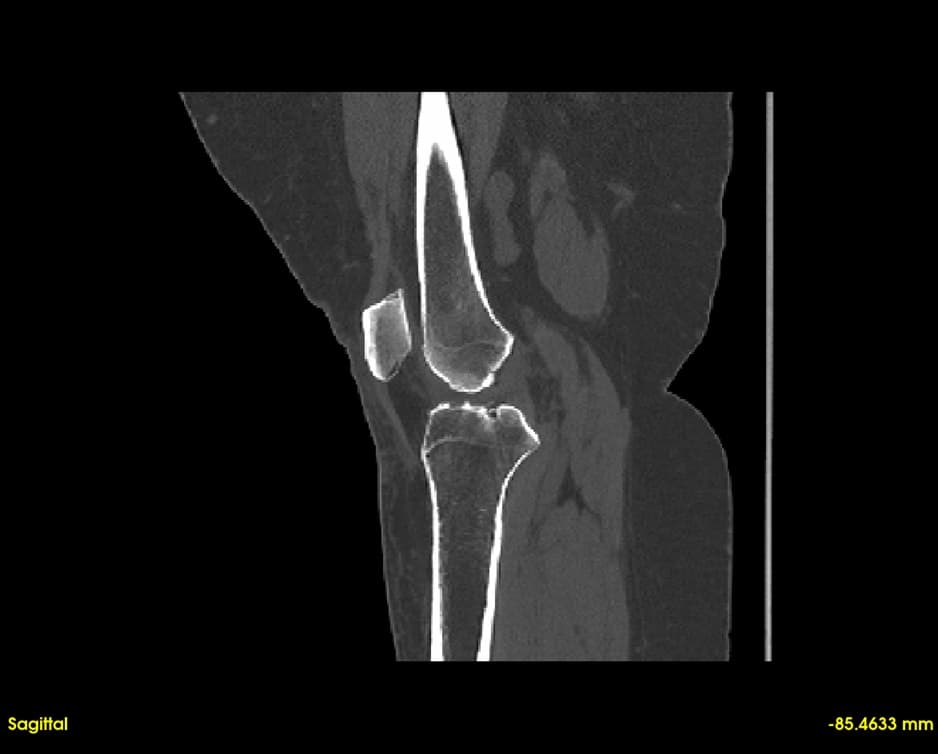

Simultaneous axial, sagittal, and coronal views. Navigate through slices with synchronized cross-referencing.

Explore slices with multi-planar reconstruction views

Quickly visualize and analyze anatomical structures from CT and MRI scans. Identify abnormalities with precise 3D visualization.